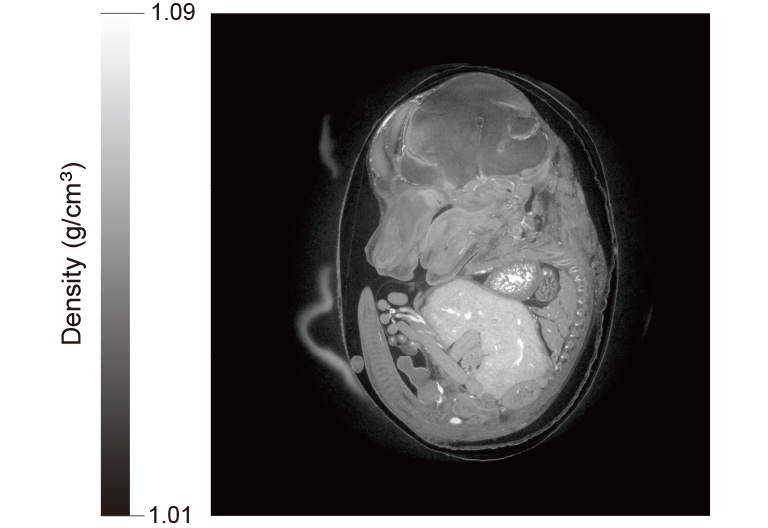

对于 X 射线或其他高能粒子的成像,通常使用连接了闪烁体的科学相机。成像系统必须需要低噪声和高速度来检测瞬时现象。

小鼠胚胎X射线相差CT图像

ORCA-Quest结合高分辨率X射线成像系统 (M11427) 生成的小鼠胚胎的X射线相差CT图像

曝光时间:15毫秒,总测量时间:6.5分钟

数据来源:SPring-8 BL20B2 beamline by Dr. Masato Hoshino, Senior scientist in Japan Synchrotron Radiation Research Institute (JASRI)